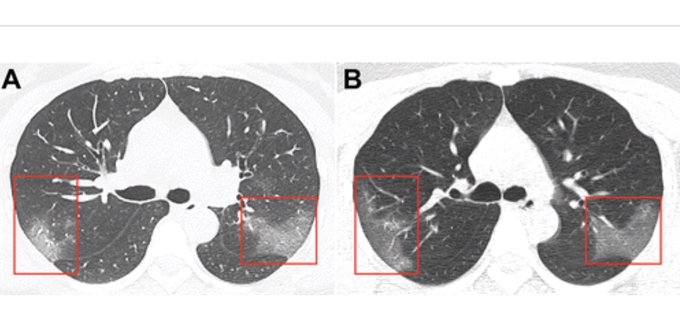

The images published by Chinese doctors, and reviewed by the Sputnik agency, are from a 33-year-old woman who entered the hospital after presenting symptoms such as fever and cough for five days.

When the woman was admitted, doctors observed that her body temperature had risen to 39 ° C and heard that the sounds of her breathing were harsh in both lungs.

According to the results of the studies published in the journal Radiology, the patient had a clear deficiency of white blood cells, in addition to multiple peripheral opacities in frosted glass in both lungs.